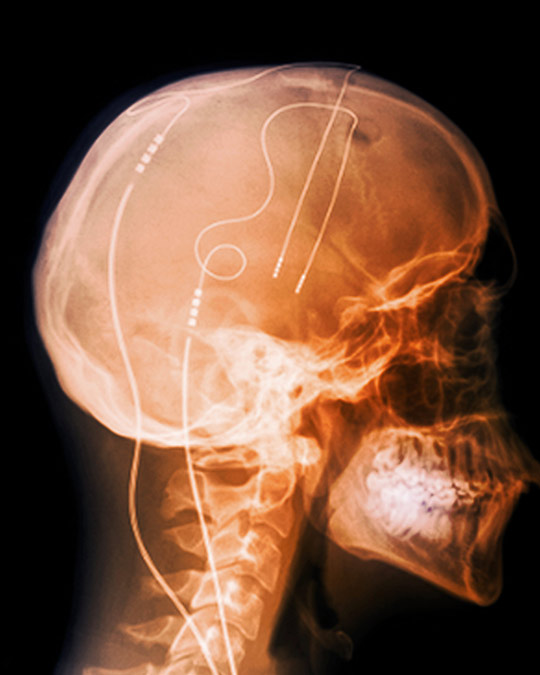

Dyp hjernestimulering i basalgangliene kan gi god symptomkontroll ved alvorlig Tourettes syndrom.

Illustrasjonsfoto: Science Photo Library